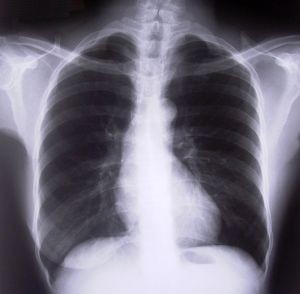

1.Tüdőrák:  A kezdeti fázisban nem észlelhetőek tünetek, ezért nagyon fontos részt venni az éves szűrővizsgálatokon. Később tartós köhögés, légszomj utalhat a betegségre. Elég gyorsan átterjed a májra, ekkor már áttétről van szó. Ez már könnyebben felismerhető: erős hastáji fájdalom, sárgult szemfehérje.